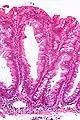

Micrograph of a sessile serrated lesion. H&E stain.

SSLs are diagnosed by their microscopic appearance; histomorphologically, they are characterized by (1) basal dilation of the crypts, (2) basal crypt serration, (3) crypts that run horizontal to the basement membrane (horizontal crypts), and (4) crypt branching. The most common of these features is basal dilation of the crypts.

Unlike conventional colonic adenomas (e.g. tubular adenoma, villous adenoma), they do not (typically) have nuclear changes (nuclear hyperchromatism, nuclear crowding, elliptical/cigar-shaped nuclei).